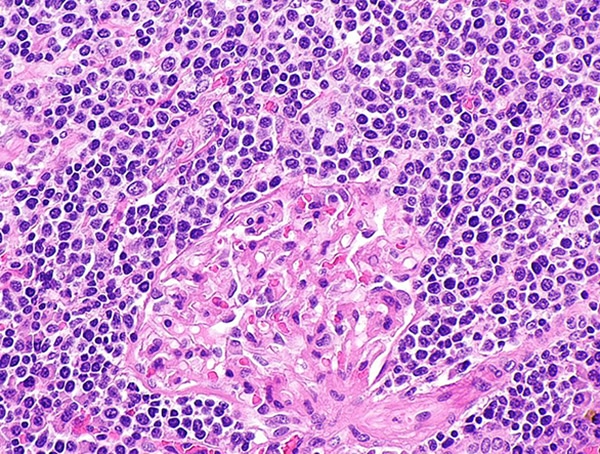

Marginal zone lymphoma. Image by Librepath via Wikimedia.

There are five different types of MZL, characterized by where they originate. MZL represents about 5 to 10 percent of all lymphomas.